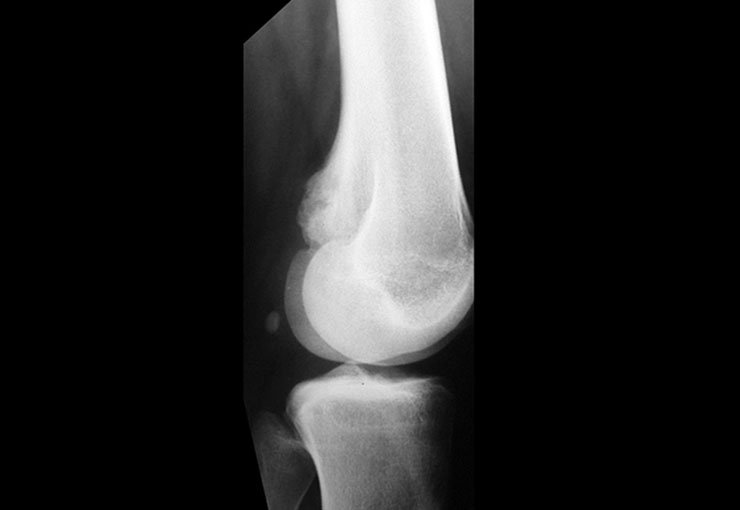

Condroblastoma O condroblastoma é uma neoplasia benigna rara que corresponde a aproximadamente 1,8% de tod...